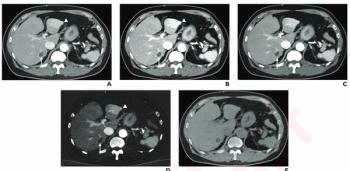

Facilitating timely detection and follow-up management of patients with aortic aneurysms, the PRAEVAorta2 software reportedly enables automated measurement of aortic diameters on computed tomography (CT) scans.

In a study involving over 500 patients, researchers noted that the CT-based AI software led to a 24 percent increase of evaluations for aortic abdominal aneurysms within six months of detection.